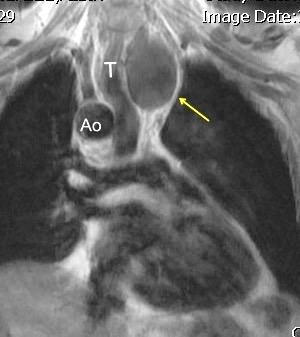

92. FIBROSO. TUMOR MEDIASTÍNICO

Tumores pluripotenciales con componentes fibroblásticos o miofibroblásticos. Hemangiopericitoma es parte de estos tumores.

Histologicamente hay variantes “sin patrón”, otros “hemangiopericitomalike”, angiofibroma-like, fibrosarcoma-like o esclerosante difuso.

Chick. JFB Solitary Fibrous Tumors..AJR 2013